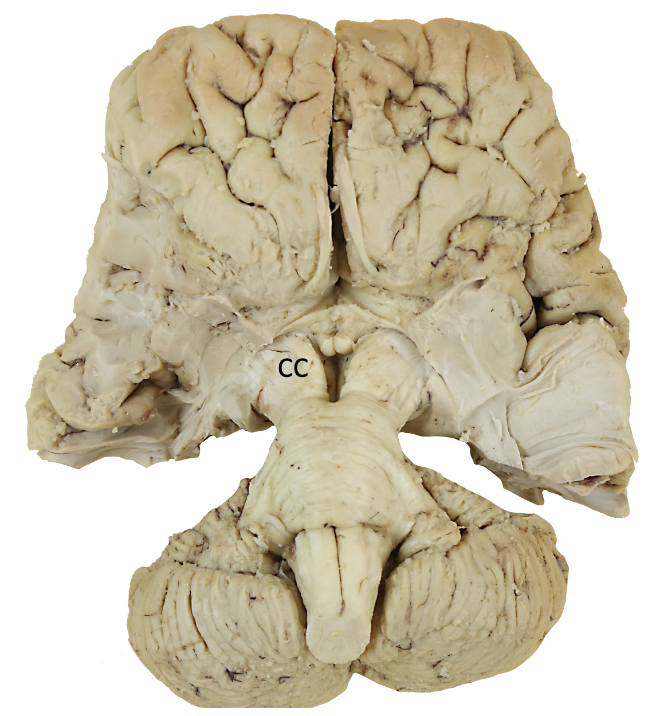

<p><strong>cc?</strong></p>

crus cerebri